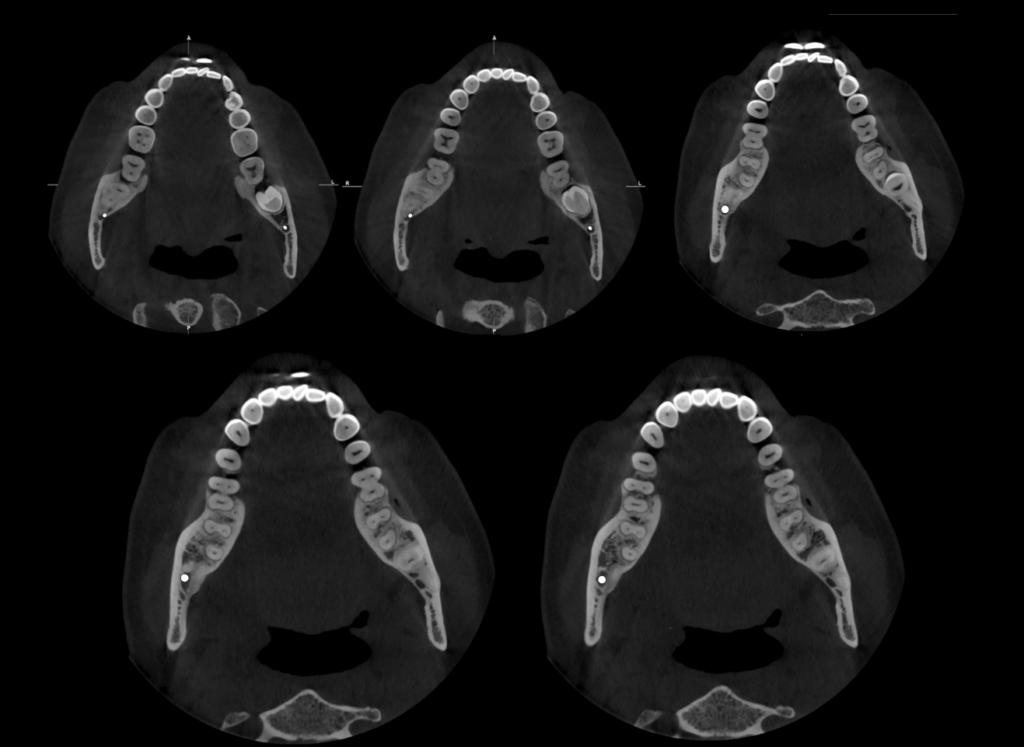

A la evaluación de la tomografía computarizada del motivo de consulta que fue la pieza 48 se observa impactada contra la superficie cervicodistal de la pieza 47, asimismo se observa la presencia de una raíz supernumeraria por vestibular y por mesial (paramolaris), la

hipercementosis de los tres segmentos, así como la dilaceración de los mismos a predominio de la raíz supernumeraria. Finalmente, el conducto dentario inferior recorre por lingual de la raíz distal y por el medio de ambas raíces mesiales, contactando con los ápices.

CORTES AXIALES